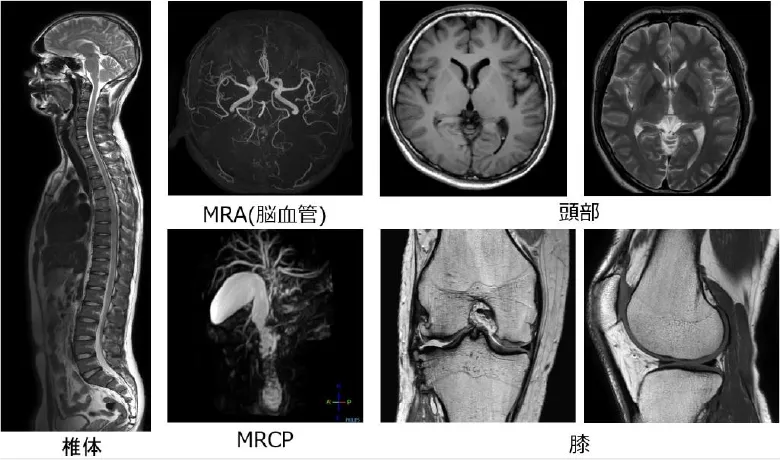

フルデジタル3.0T MRI装置

今回、新たに最新鋭の3.0TMRI装置が導入されました。MRI装置は強力な磁石と電波を利用して人体の様々な断面を撮像する装置です。特に脳や脳血管、脊椎、四肢、腹部などの病変に関しては圧倒的な検査能力をもっています。X線撮影では描出することが難しい血管、靭帯、軟部組織、臓器などの描出に優れているため、当院の脳外科では「脳梗塞」、「脳出血」、「脳腫瘍」、「脳動脈瘤」、「血管狭窄」など、整形外科では「椎間板ヘルニア」、「靭帯損傷」、「半月板損傷」、「腱板断裂」など、外科では「胆石」、「胆管拡張・狭窄」などを診断するのに役立っています。

本装置は業界で唯一のデジタルコイルシステムにより、大幅な画質向上を実現し、より高精細でより診断に有用な画像情報を提供できるようになりました。